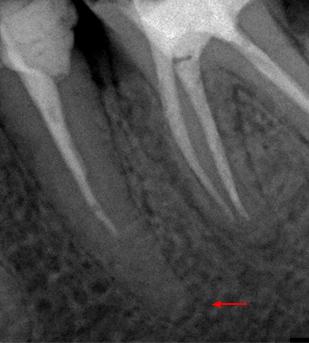

Пациент 45 лет направлен лечащим доктором на перелечивание 35 зуба.

Со слов пациента эндодонтическое лечение проводилось три года назад.

На рентгенологических снимках представлена картина до лечения, диагностический снимок и конечный результат.